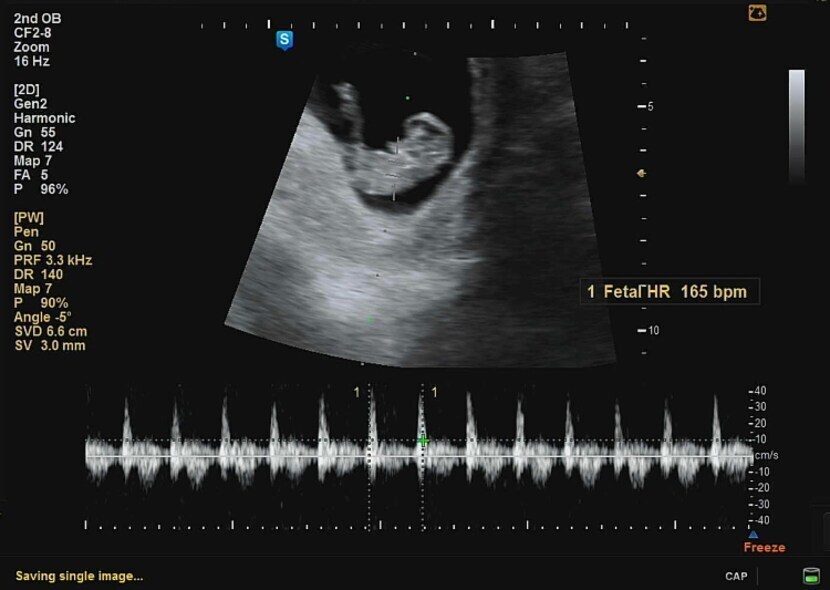

μ¬μ₯λ κ½λ±κ½λ±